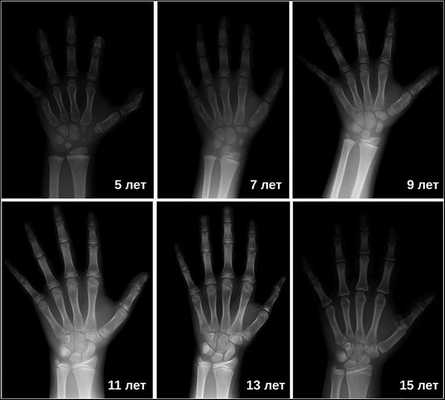

Рентгенография турецкого седла выявляет его детскую форму («стоячий овал») и широкую (т. н. ювенильную) спинку. При увеличении размеров турецкого седла и наличии участков обызвествления, в первую очередь, следует думать об опухоли. Рентгенография лучезапястных суставов и кистей позволяет определить рентгенологический («костный») возраст. При гипофизарном нанизме отмечается значительное замедление процессов окостенения скелета.

Затем врачи определяют костный возраст. Сделать это можно с помощью рентгена или УЗИ запястья. В норме костный возраст может отставать или опережать паспортный на два года.

Инструментальные исследования: осмотр глазного дна (возможны дефекты полей зрения, изменения глазного дна), ЭКГ (низкий вольтаж зубцов, брадикардия, нарушение реполяризации), рентгенография лучезапястного сустава (отставание на 4 более лет от хронологического).

10. Рентгенография лучезапястных суставов.